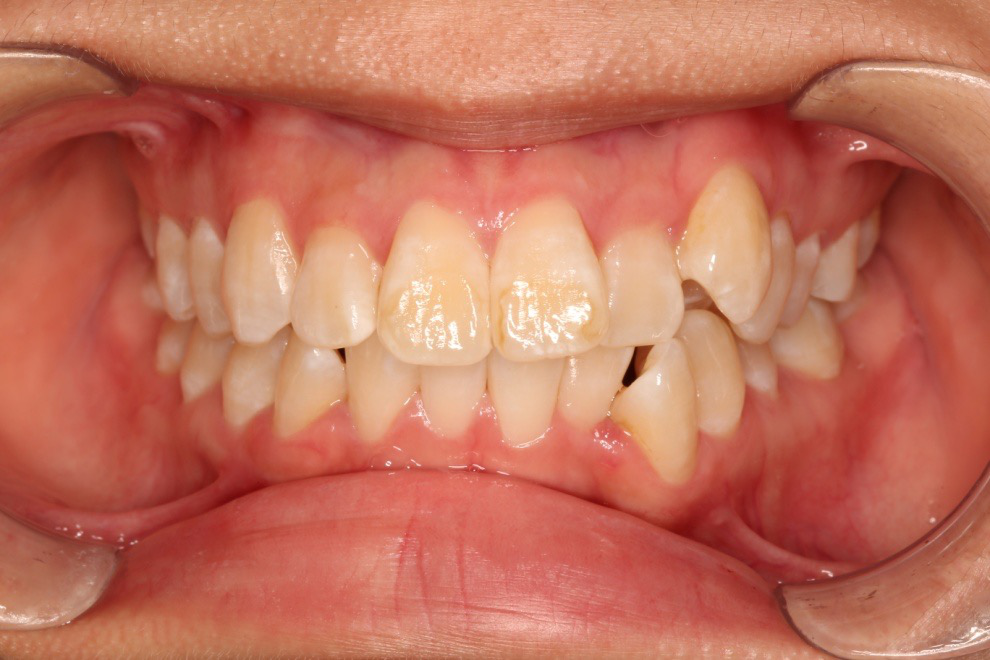

2018.11.14  术后侧面改善明显,露龈笑改善明显,笑弧笑线协调,颏部肌肉紧张度明显改善

2018.11.14  术后磨牙尖牙I类关系,中线齐,覆合,覆盖正常

宏观评价:面部对称,面下三分一比例协调,上下唇凸度正常,上颌牙列内收转矩控制良好,下颌后缩改善,颏唇沟变得更加柔和,术后达到基本直面型。

迷你观评价:上下牙齿中线与面中线对齐,笑弧协调,微笑时牙龈暴露量正常,微笑时横向正常,左右唇基本对称。

微观评价:牙齿整齐,咬合关系良好,上下前牙转矩及突度控制良好,磨牙关系I类,尖窝咬合关系良好,OB,OJ正常。